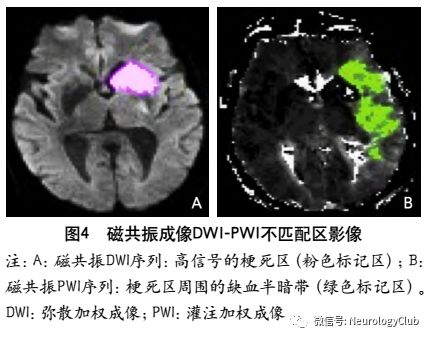

MRI PWI常采用动态磁敏感对比增强技术,通过对比剂团注追踪技术进行动态增强扫描,依靠对比剂磁化率改变引起信号变化的原理成像。经处理后可得出相应灌注成像的参数如CBF、CBV、MTT及TTP等。研究表明,CBF下降和MTT延长是组织缺血的相对敏感指标,但存在过分估计最终梗死体积的可能性;TTP图像上脑灰质、白质之间无明显区别,可以清楚显示病变的范围和边界。虽然目前识别缺血半暗带的方法有多种,但MRI DWI与PWI不匹配区是急诊过程中判断缺血半暗带较切合实际的方法(图4)。一项回顾性研究认为,PWI的病灶面积是DWI病灶面积的2.6倍时早期再灌注的治疗效果最好